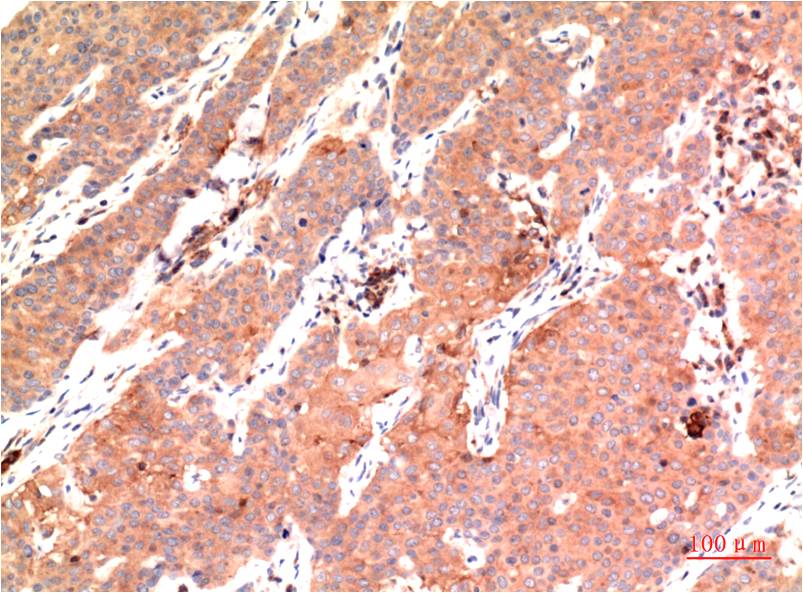

- Immunohistochemistry analysis of paraffin-embedded Human Colon Carcinoma Tissue using epsilon Tubulin antibody.High-pressure and temperature Sodium Citrate pH 6.0 was used for antigen retrieval.